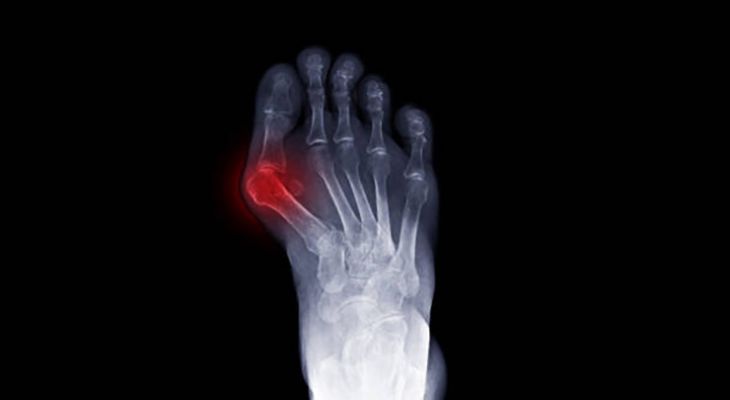

Hallux valgus - vbočený palec

Vbočený palec (hallux valgus) je patrně nejčastější deformitou nohy. Deformita může vzniknout už v dětství jako zděděná odchylka. Nejčastěji vzniká v pozdějším věku, ale není výjimkou již kolem 20 - 30. roku věku. V důsledku ochabnutí či méněcennosti vazivového a svalového aparátu dojde k poklesu podélné i příčné klenby. Vlivem přetížení vnitřní strany nohy při vbočeném postavení paty a hlezenního kloubu dojde k přetížení palcové strany nohy. Dále dojde k ochabnutí a uvolnění meziprstních svalů, rotaci palce a postupně rozšíření přední části nohy. Tah svalů a šlach pak stahuje palec do vbočeného postavení, mění se osa palce. Tlakem obuvi vzniká otlak na kůži i zhrubění na kosti. Postupně vznikají degenerativní změny na základním kloubu palce.